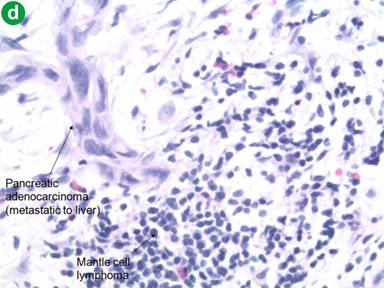

On follow-up in May 2012, the patient reported feeling generally well, except for a new onset of abdominal discomfort, occurring 30 minutes after eating, lasting for 30-60 minutes and associated with diarrhea. He did not complain of other new symptoms. A PET/CT after eight cycles of chemotherapy indicated a near-complete disappearance of the disease at the level of spleen and lymph nodes, but a new mass at the tail of the pancreas measuring 2.0x2.5 cm (Figure 2). Several small (5 mm) hypodense lesions were noted in the liver. These findings were not present on the PET/CT done after the sixth cycle of chemotherapy. To evaluate the focal area of persistent uptake in the pancreatic tail, a CT scan was done in June 2012. It confirmed the mass in the tail of the pancreas, highly suspicious for malignancy (Figure 3). His anemia and thrombocytopenia remained stable. The white blood cell count was within normal range, but showed persistently decreased absolute lymphocyte count. Serum IgG and IgM immunoglobulin levels were decreased to 642 mg/dL (reference range: 782-1,195 mg/dL) and 31 mg/dL (reference range: 53-334 mg/dL), respectively. Serum IgA was normal. CA 19-9 level was elevated at of 1,177 U/mL (reference range: 0-30 U/mL). Biopsy of the pancreatic mass revealed poorly differentiated adenocarcinoma (Figure 4). Immunohistochemical stains of the biopsy specimen revealed positive pankeratin, CK7, CA 19-9, BerEP4, CEA and p63 markers, suggesting primary adenocarcinoma of the pancreas. The patient was considered for possible distal pancreatectomy. However, a preoperative laparoscopic exam showed multiple liver and peritoneal tumor implants, with a biopsy showing pancreatic adenocarcinoma (Figure 4). In addition, the liver biopsy revealed an adjacent atypical lymphoid infiltrate consistent with the patient’s previous mantle cell lymphoma, staining positive for CD20, CD5, BCL-2 and cyclin D1 (Figure 4). The close proximity of the metastatic pancreatic cancer lesions and the mantle cell lymphoma infiltrate was consistent with collision tumors in the hepatic parenchyma (Figure 4).

Figure 4. Pathology microphotographs of the liver core biopsy. a. Liver biopsy specimen showing a diffuse monomorphic infiltrate of small-to-medium sized lymphocytes and adjacent metastatic poorly differentiated pancreatic adenocarcinoma (H&E, 4x magnification). b. Mantle cell lymphoma showing positive staining for cyclin D1 immunohistochemical stain (H&E, 4x magnification). c. Liver biopsy showing a diffuse monomorphic infiltrate of small-to-medium sized lymphocytes and adjacent metastatic poorly differentiated pancreatic adenocarcinoma (H&E, 20x magnification). d. Liver biopsy showing a diffuse monomorphic infiltrate of small-to-medium sized lymphocytes and adjacent metastatic poorly differentiated pancreatic adenocarcinoma (H&E, 40x magnification).